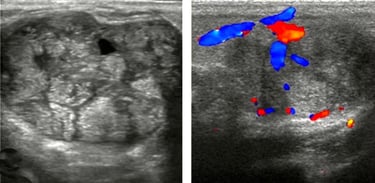

Hands-on sessions emphasize a systematic imaging protocol that covers normal tissue assessment, variant patterns, and subtle abnormalities. You’ll practice with focused coaching on image optimization, Doppler utilization, and documentation that supports meaningful clinical communication.